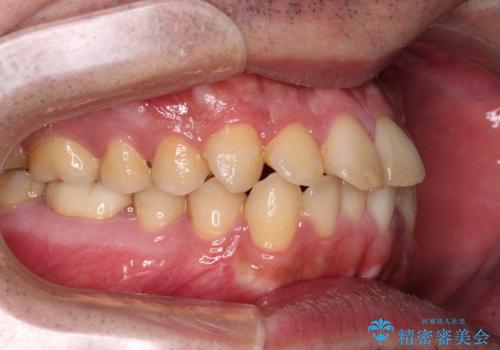

- 前歯のデコボコを治したいとのことで来院された患者様です。

できる限り楽して、短期間で治したいとのことで、ワイヤー装置にて矯正治療を行うこととしました。